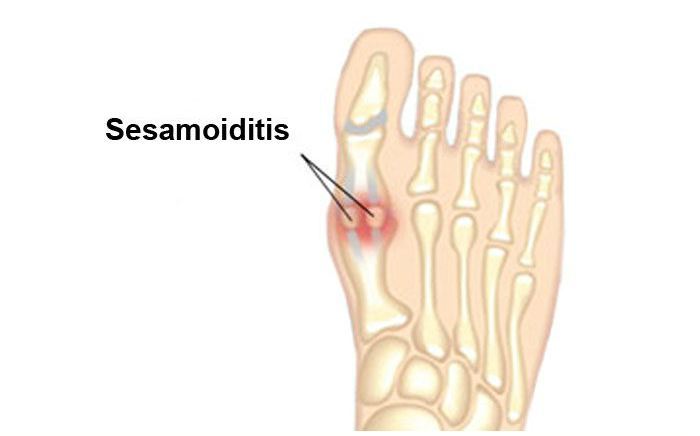

Common Foot & Ankle Disorders

Did you know the foot has 26 bones, 33 joints, 107 ligaments, 19 muscles, and numerous tendons? These parts all work together to allow the foot to move in a variety of ways while balancing your weight and propelling you forward or backward on even or uneven surfaces. It is no wonder that 75 percent of all Americans will experience foot problems at one point or another in their lifetimes.